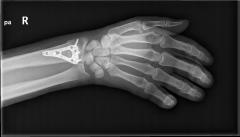

Υπάρχουν διάφορες χειρουργικές τεχνικές και υλικά που χρησιμοποιούνται, ανάλογα με τη μορφολογία του κατάγματος. Μετεγχειρητικώς ενδέχεται να εφαρμοστεί ολιγοήμερη ακινητοποίηση. Εαν απαιτηθεί φυσιοθεραπεία, αυτή είναι καλό να γίνεται μετά την 6η μετεγχειρητική εβδομάδα.

Περίπτωση 2ου ασθενούς